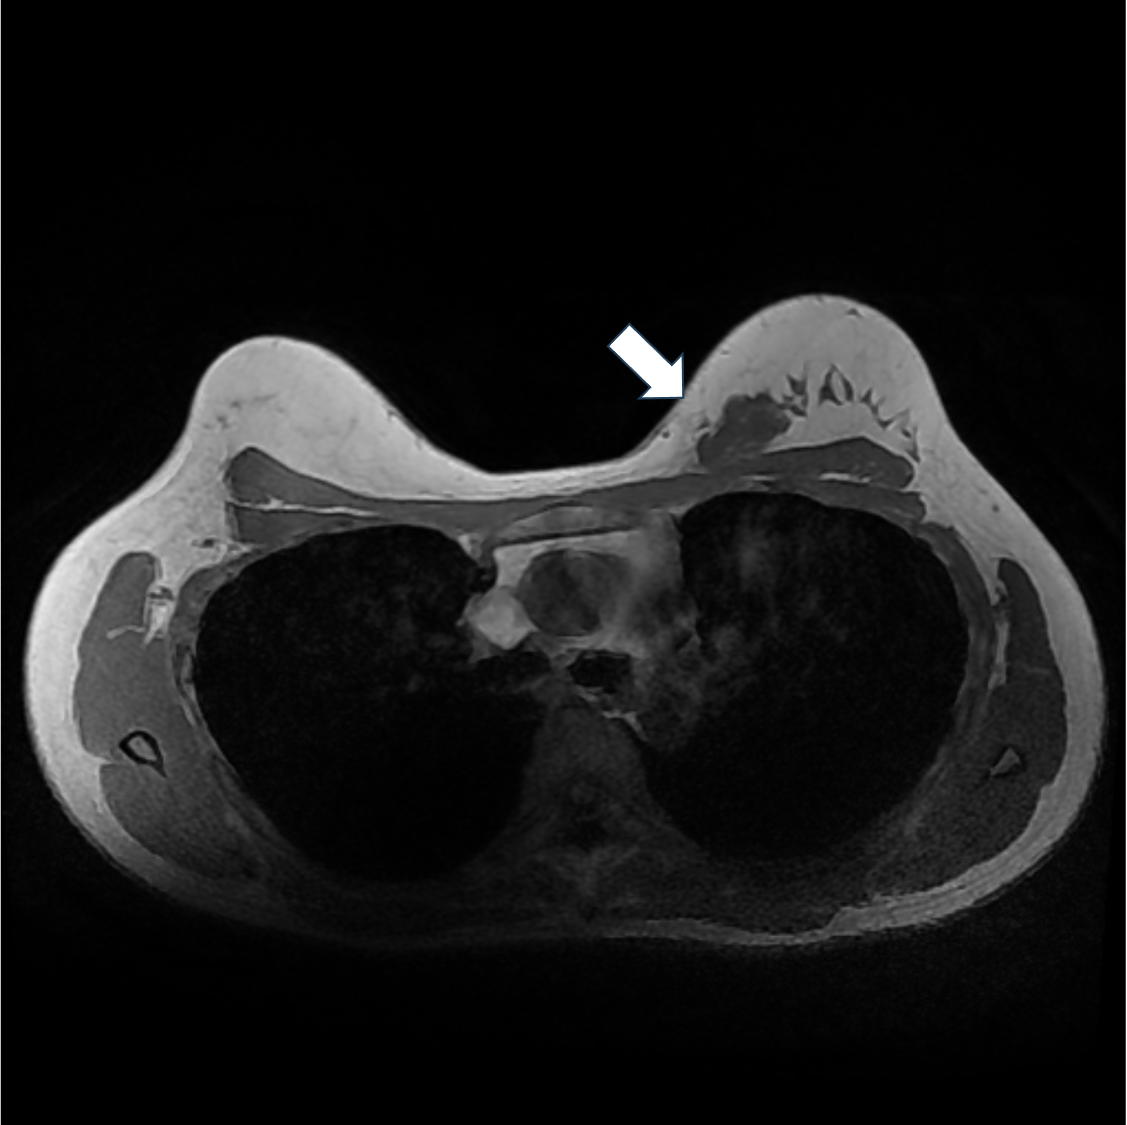

1. T1強調画像(造影前)

左乳房A区域にT1強調画像低信号を示す不整形腫瘤を認める。